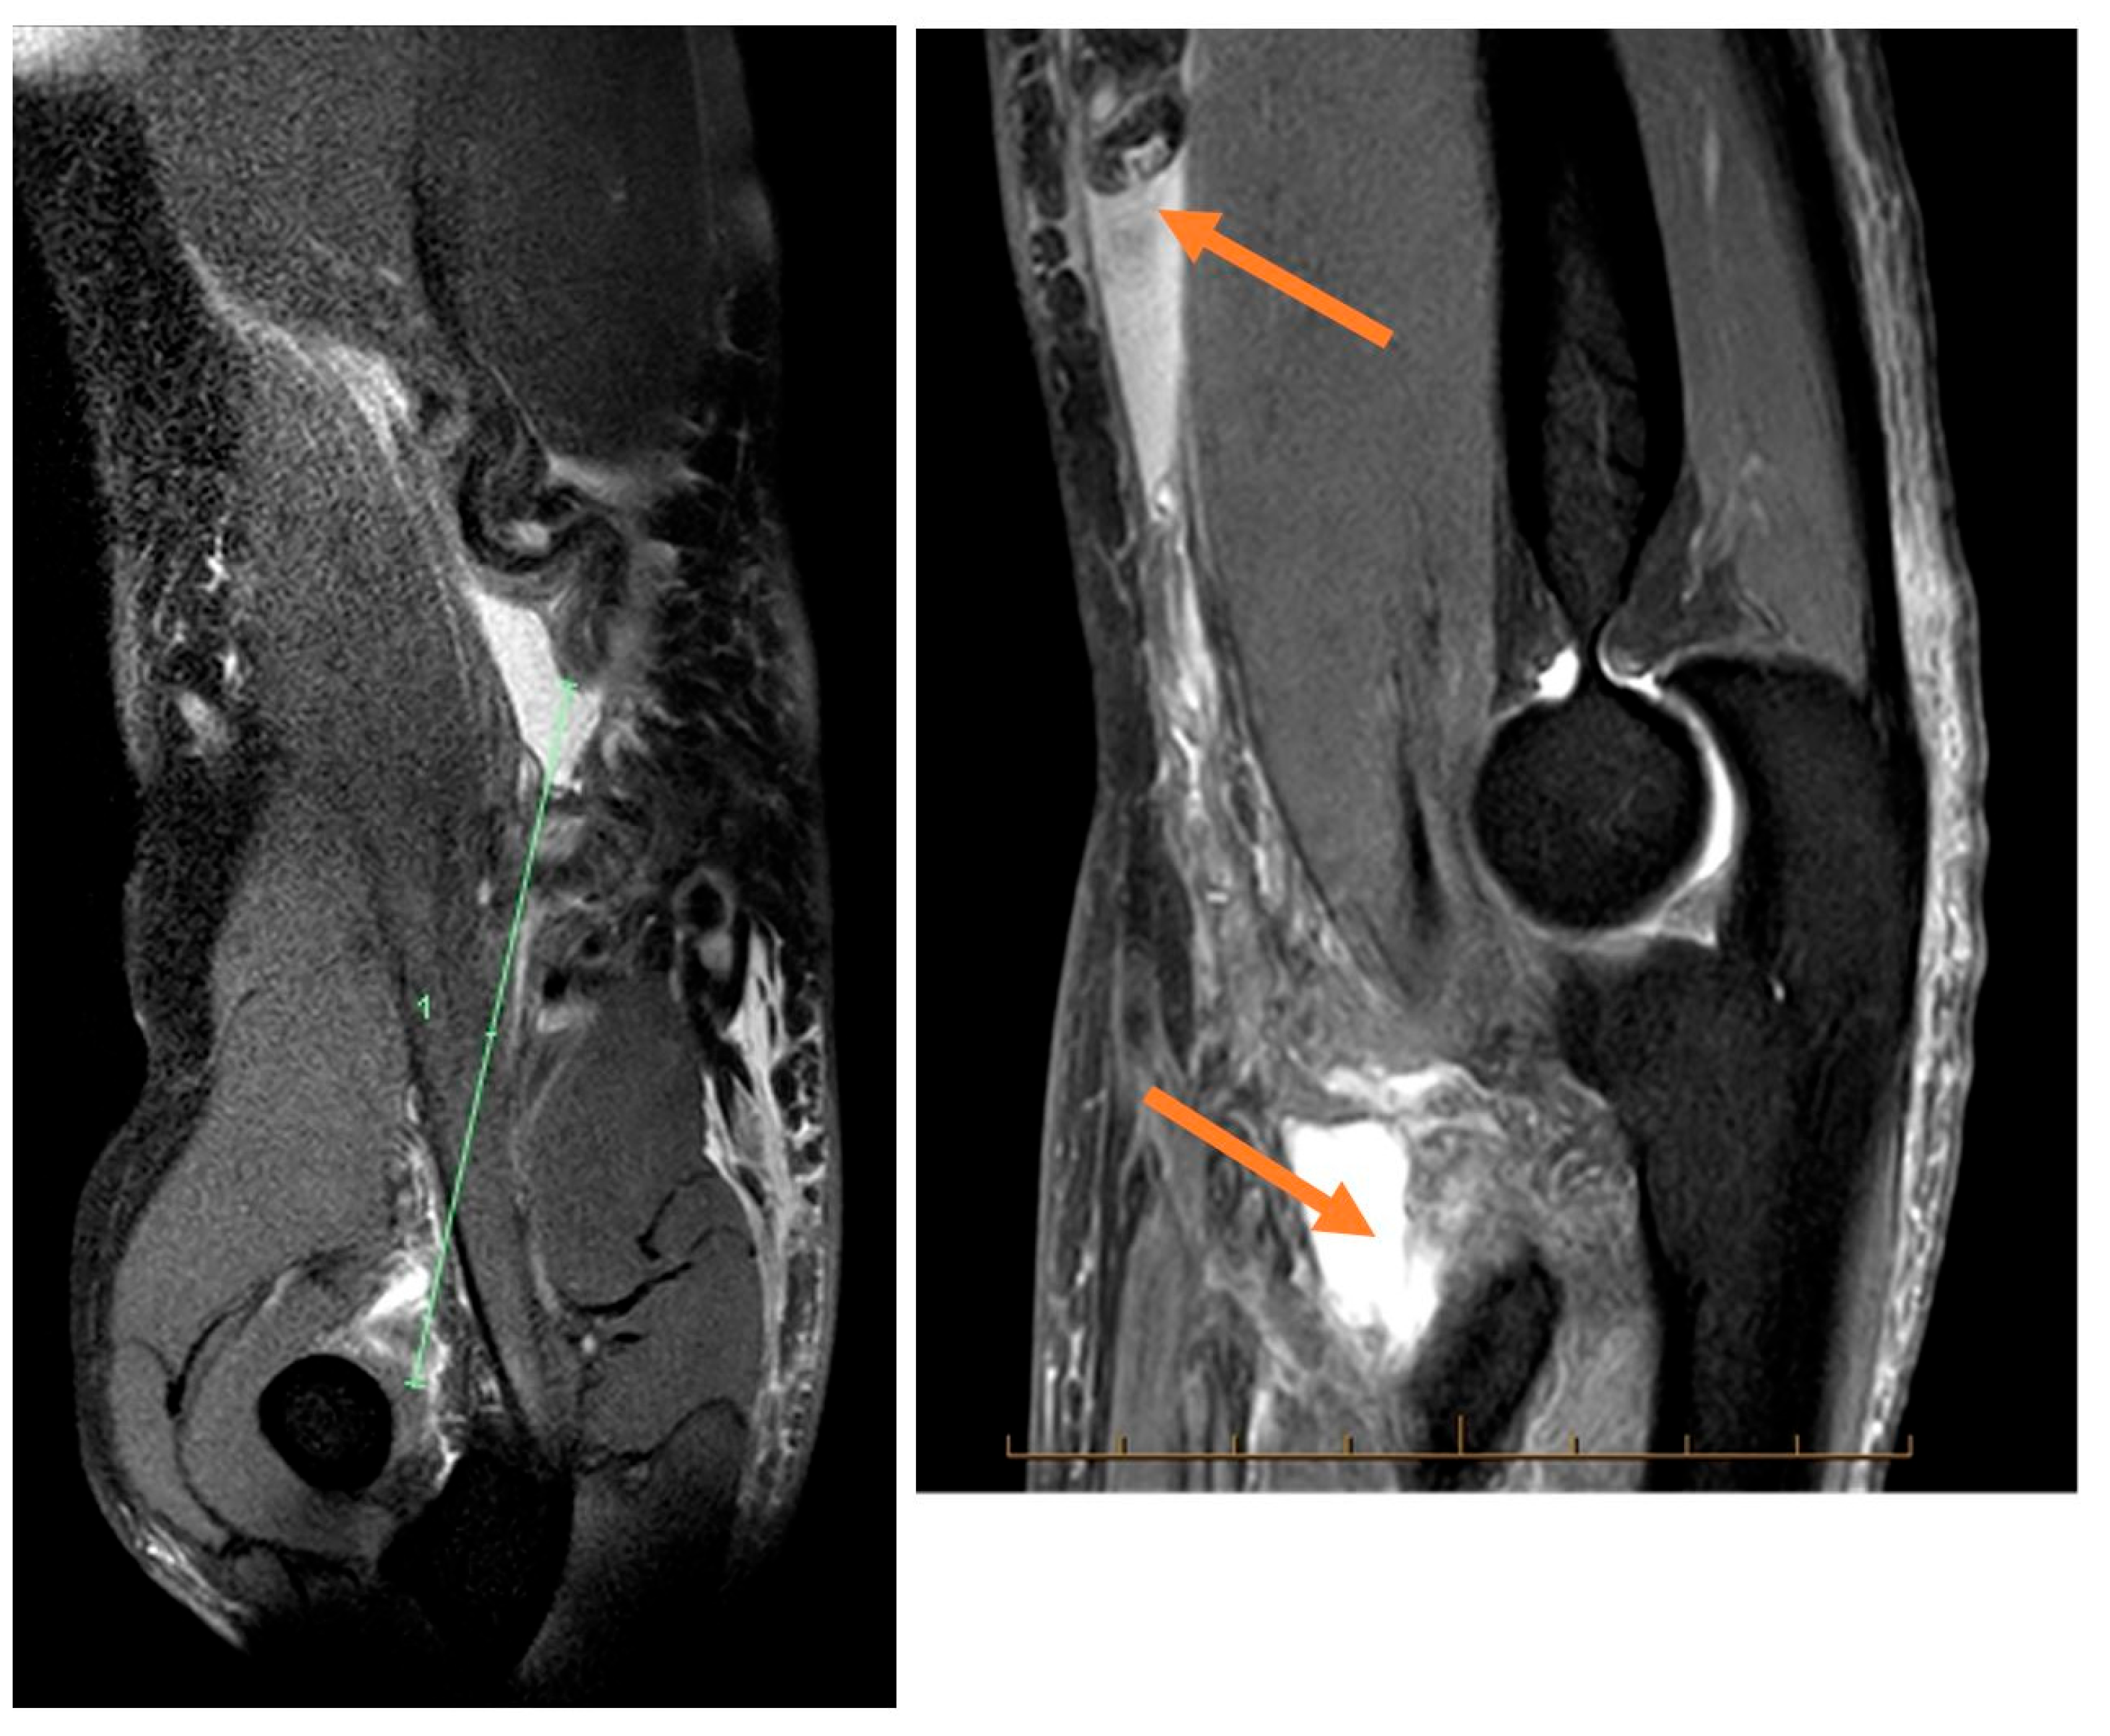

Paraclinical investigation: MRI (Figure 1) is the gold standard as far as paraclinical imaging goes, but musculoskeletal ultrasound is also a good option for imaging diagnosis in the case of distal biceps tendon ruptures, X-rays can also be used for imaging diagnosis but are not as efficient as the previous methods.

Figure 1. Distal biceps tendon MRI.